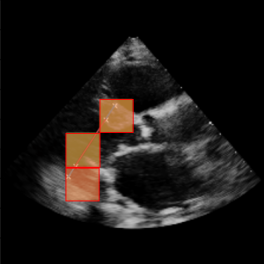

Left Ventricular Hypertrophy (LVH), one of the leading predictors of adverse cardiovascular outcomes, is the condition where heart’s mass abnormally increases secondary to anatomical changes in the Left Ventricle (LV) [10]. These anatomical changes include an increase in the septal and LV wall thickness, and the enlargement of the LV chamber. More specifically, Inter-Ventricular Septal (IVS), LV Posterior Wall (LVPW) and LV Internal Diameter (LVID) are assessed to investigate LVH and the risk of heart failure [21]. As shown in Figure 1 (a), four landmarks on a parasternal long axis (PLAX) echo frame can characterize IVS, LVPW and LVID, and allow cardiac function assessment. To automate this, machine learning-based (ML) landmark detection methods have gained traction.

It is difficult for such ML models to achieve high accuracy due to the sparsity of positive training signals (four or six) pertaining to the correct pixel locations. In an attempt to address this, previous works use 2D Gaussian distributions to smooth the ground truth landmarks of the LV [9, 13, 18]. However, as shown in Figure 1 (b), for LV landmark detection where landmarks are located at the wall boundaries (as illustrated by the dashed line), we argue that an isotropic Gaussian label smoothing approach confuses the model by being agnostic to the structural information of the echo frame and penalizing the model similarly whether the predictions are perpendicular or along the LV walls.